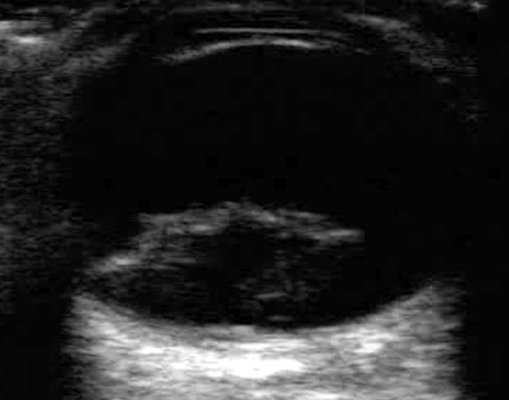

- The normal retina is continuous with other structures of the posterior eye. It is thus not visibly distinct.

- With retinal detachment, fluid enters into the space beneath the retinal epithelium. This “detaches” the retina from the posterior structures of the eye.

- The retina appears as a thick and hyperechoic “wiggly line.”